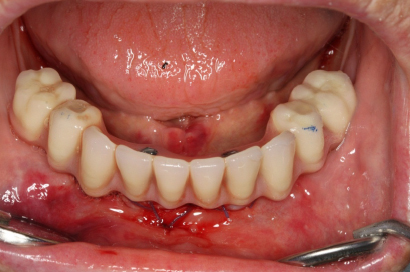

Během let může postupnou ztrátou zubů zůstat v ústech omezený počet zubů, které umožňují držení zubních náhrad.

V důsledku přetížení zbylých zubů např. houpavými pohyb snímacích náhrad dochází k uvolnění těchto zubů a držení můstků a protéz je tak velmi těžké. V těchto případech můžeme pomocí implantátů zvýšit počet pilířů a tím zabránit přetěžování a ztrátě zbylých zubů

Bezzubá čelist je hlavní indikací pro ošetření pomocí implantátů. Zejména celkové zubní náhrady v dolní čelisti mají velice nízkou stabilitu a držení díky velkému úbytku kosti.

S pomocí zubních implantátů můžeme díky různým kotevním systémům (třmeny, kulové hlavy, Locatory) zajistit stabilitu a držení protézy nebo při použití většího počtu implantátů zhotovit pevné náhrady – můstky nalepené nebo našroubované na pevno na implantáty.